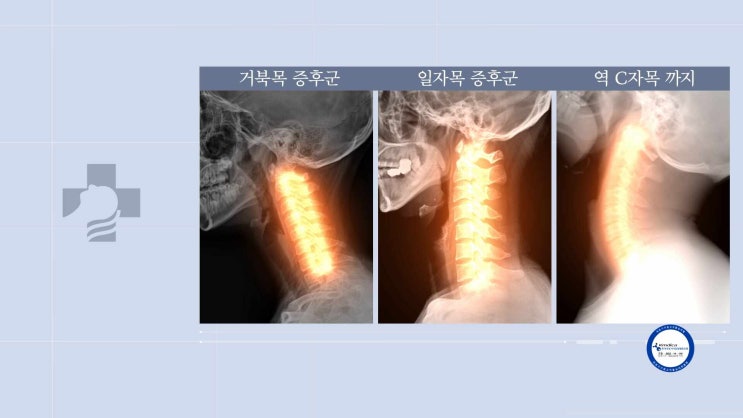

지금 당신의 목은 어떻습니까? 당신의 베개는 편하십니까? #거북목, 일자목증후군으로 고생하시나요? 피곤...

경추베개, 네큐어 메디컬필로우가 필요한 이유!-거북목 치료 등에 도움!

#거북목 증후군, 일자목 증후군, 추간판(디스크) 탈출증, 퇴행성 협착증~~ 잠 못 드는 밤을 보내고 있는 당...